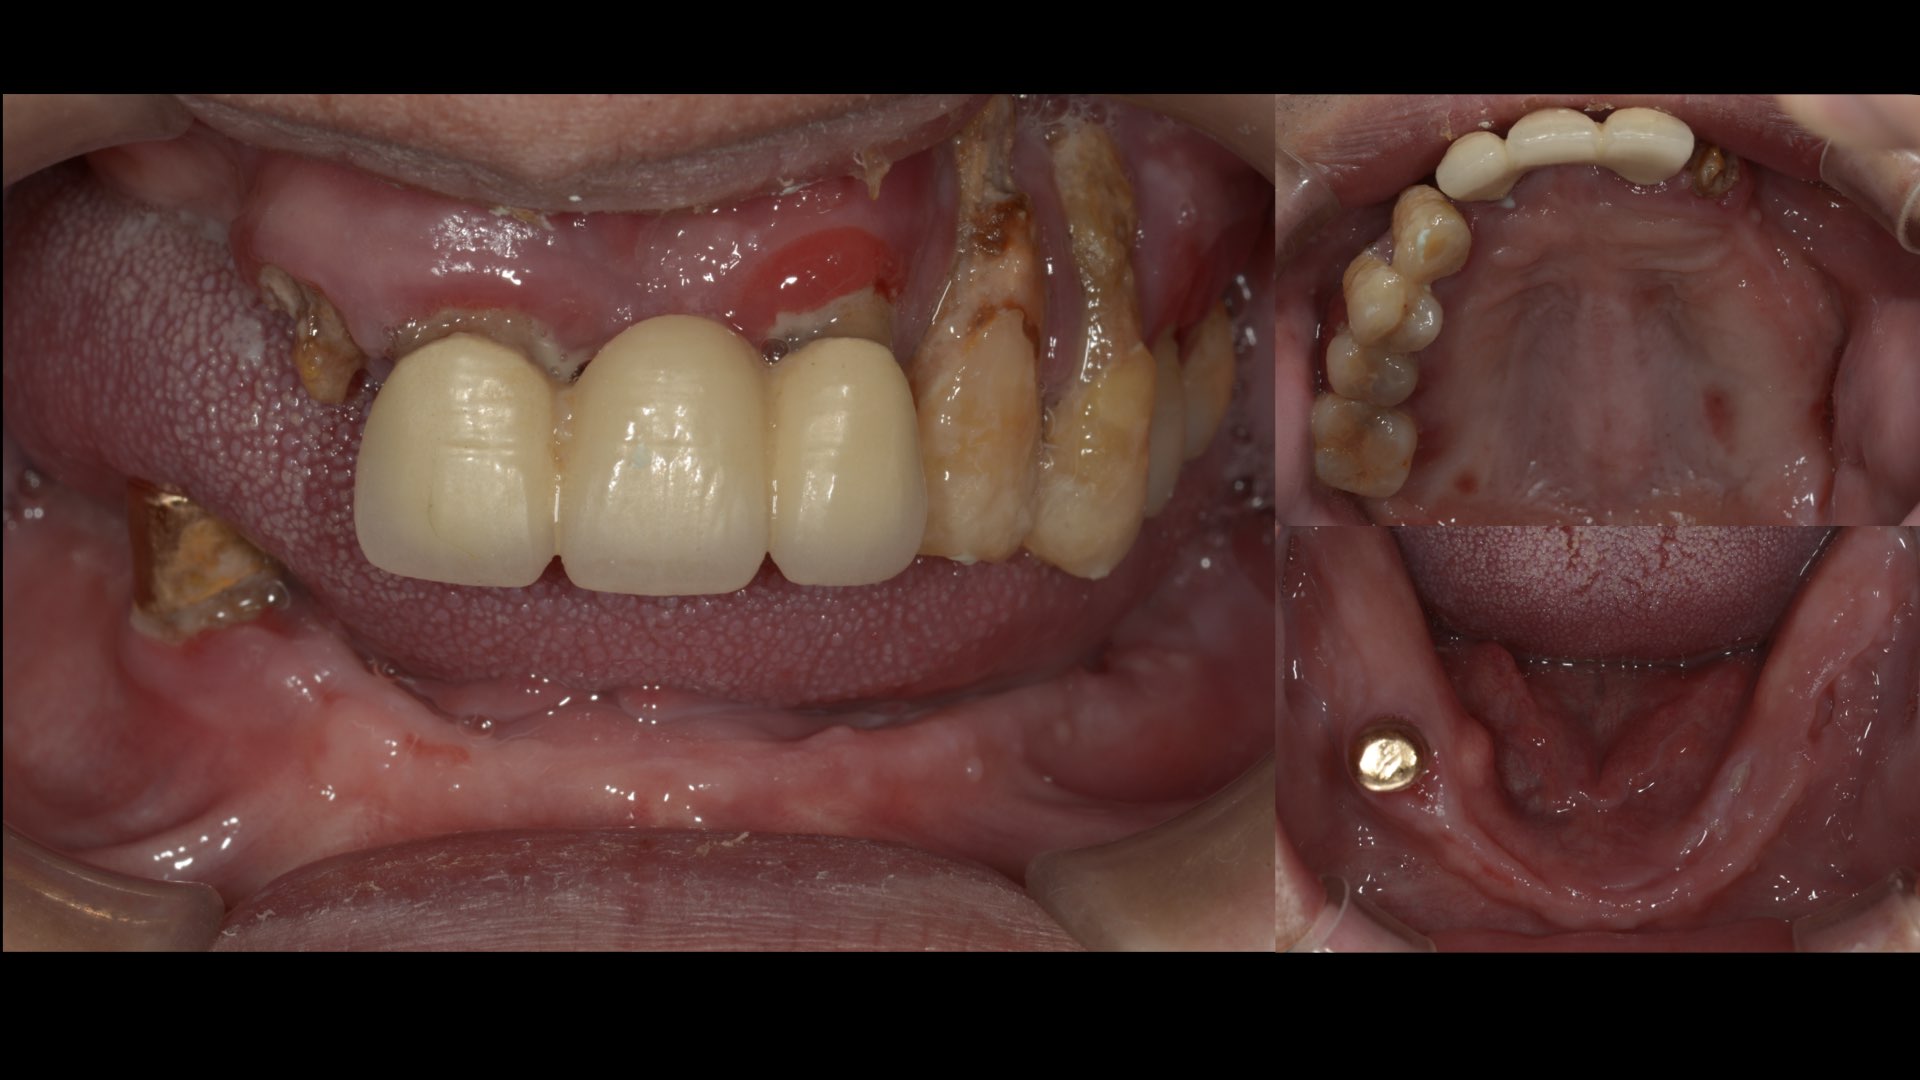

陳大哥經朋友介紹來榮醫師,長期工作忙碌的他,因為沒有細心照顧,造成口腔狀況很不好,有嚴重牙周病,飲食、健康出了一些狀況。

榮醫師檢查後,除了現有活動義齒狀況不好之外,現有牙齒與牙根的狀況也不好,經討論後,活動義齒不符合平日的需求,轉而向全口植牙義齒。

嚴重牙周病